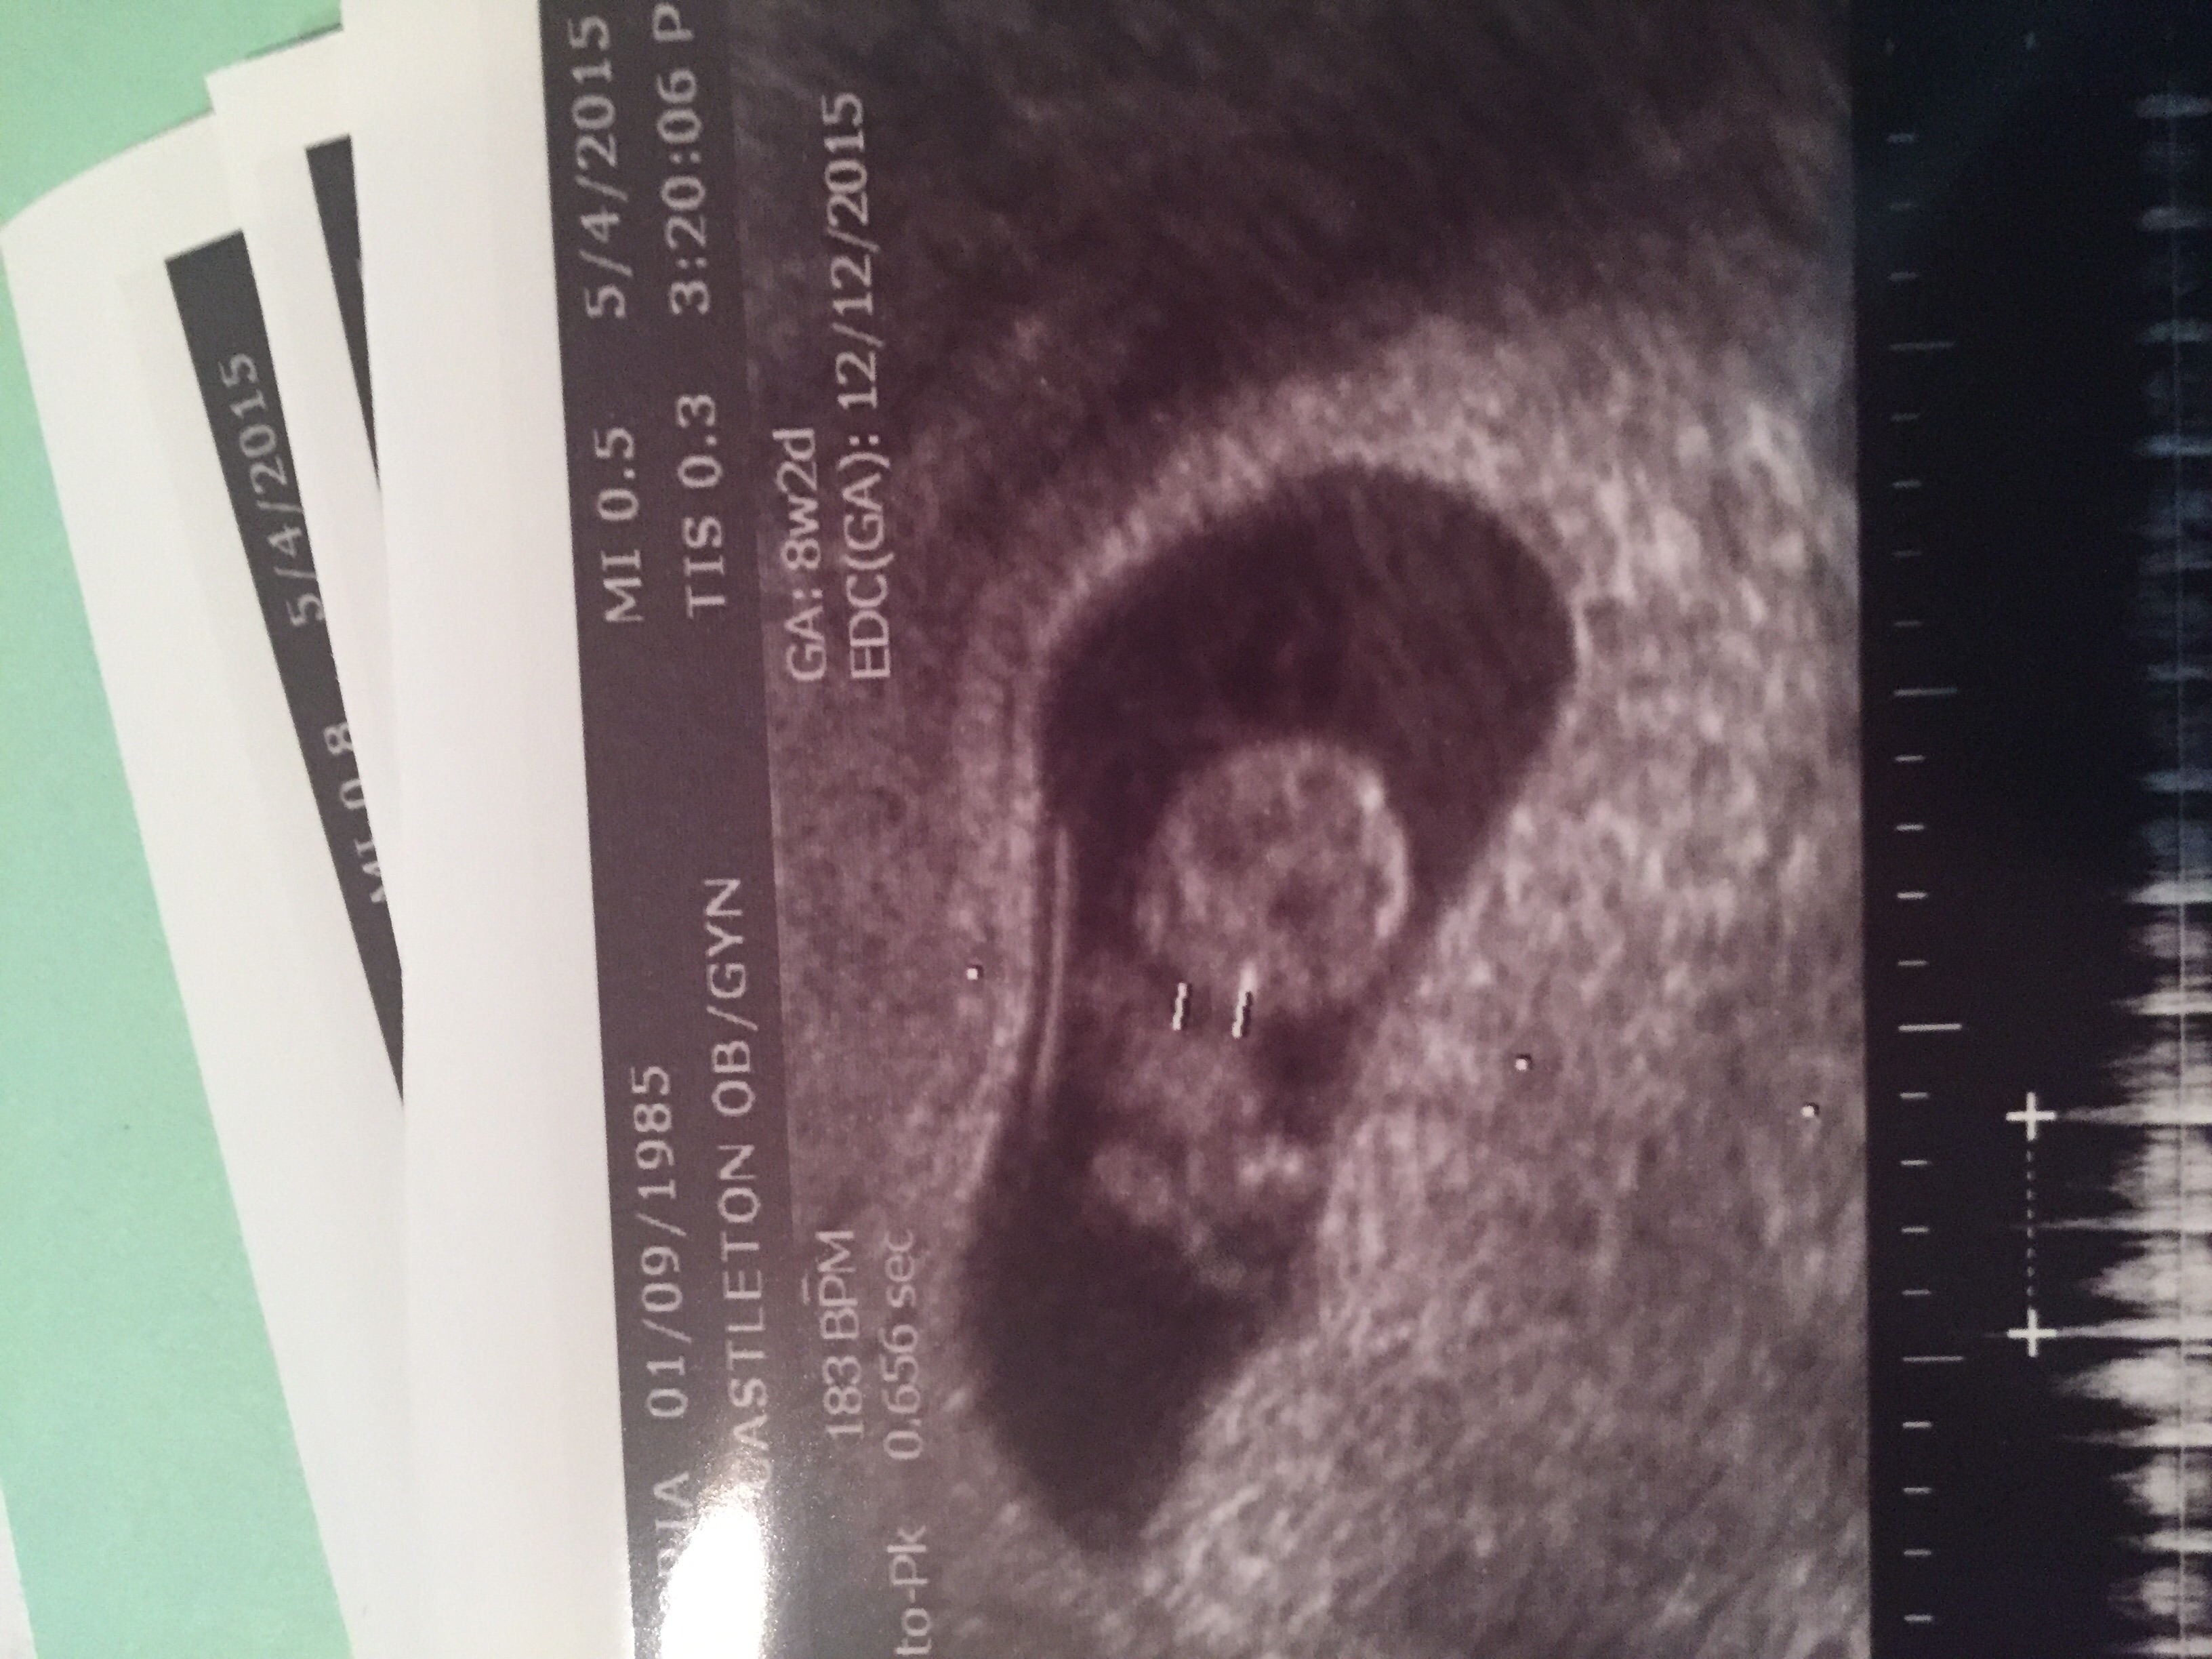

image